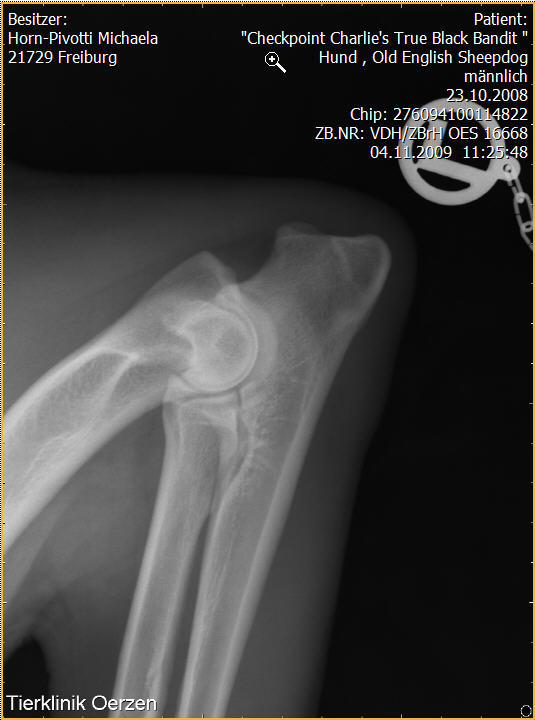

Röntgenaufnahmen HD/ED “Checkpoint Charlie’s True Black Bandit”